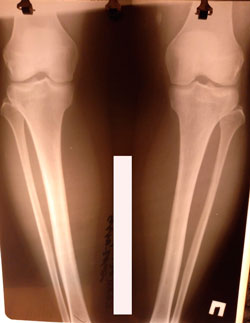

Исходник - 41 год.

Дата операции - 02.02.2021

image-03-02-21-12-32-4.jpg

image-03-02-21-12-32.jpg